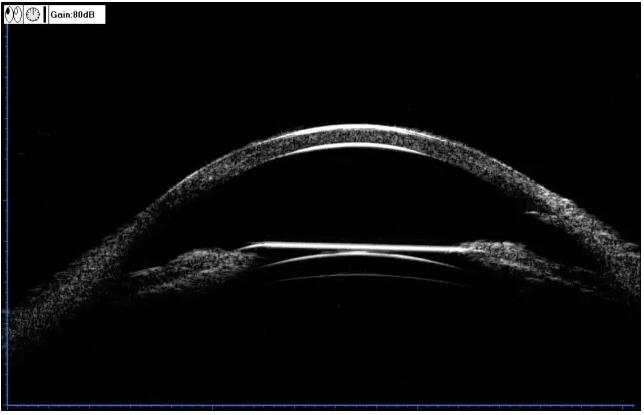

▼两个不同的患者,同样的OCT表现